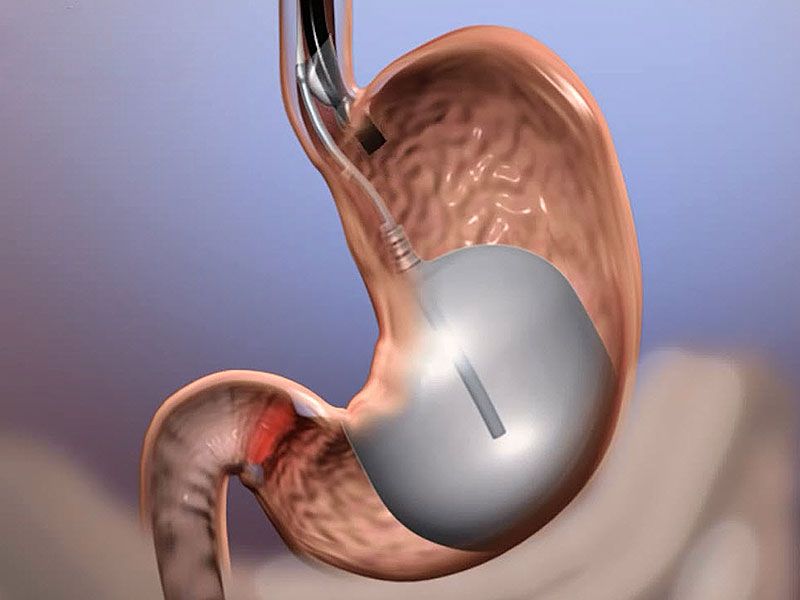

نقش کپسولهای بالون در کاهش وزن بلعیدن کپسولهای بالون به بیماران چاق کمک میکند تا میزان کمتری غذا بخورند و به طور میانگین حدود هفت کیلوگرم از وزن خود را از دست بدهند.به گفته متخصصان افراد چاقی که کپسولهای بالون را میبلعند نسبت به بیمارانی که تنها رژیم غذایی را رعایت کرده و ورزش میکنند دو برابر بیشتر وزن کم …